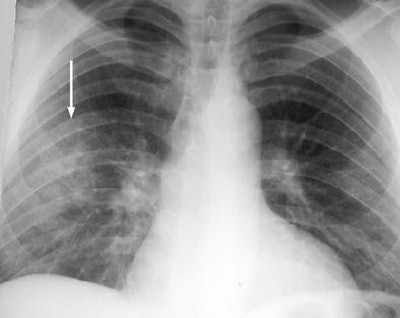

These are your lungs on crack

On x-rays, acute lung injury after cocaine use can appear as "bilateral, perihilar areas of increased opacity or attenuation, usually without pleural effusion or cardiomegaly," according to Dr. Michael Gotway and colleagues from San Francisco General Hospital; the University of California, San Francisco; and Brigham and Women's Hospital in Boston. "High-resolution CT may show multifocal ground-glass attenuation associated with septal thickening," but the condition clears up quickly after discontinuing cocaine use, they reported (RadioGraphics, October 2002, Vol. 22:4, pp. S119-S135).

| Acute lung injury (crack lung) in a 37-year-old man who presented with shortness of breath and cough after crack use. Above, frontal chest radiograph reveals ground-glass areas of increased opacity in the right lower lobe (arrow), a finding that is consistent with numerous causes, including edema, infection, hemorrhage, and aspiration. Below, high-resolution CT scan (level = -700 HU, window width = 1,000 HU) reveals ground-glass attenuation (arrows) with interlobular septal thickening (arrowheads). The differential diagnosis of these findings includes infection (especially Pneumocystis carinii pneumonia), lipoid pneumonia, and alveolar proteinosis, among numerous other causes. Bottom, frontal chest radiograph obtained two days after CT shows resolution of the increased opacity. Fig. 3a, b, c. Gotway MB, Marder SR, Hanks DK, et al. "Thoracic Complications of Illicit Drug Use: An Organ System Approach." RadioGraphics. 2002;222:S119-S135. |